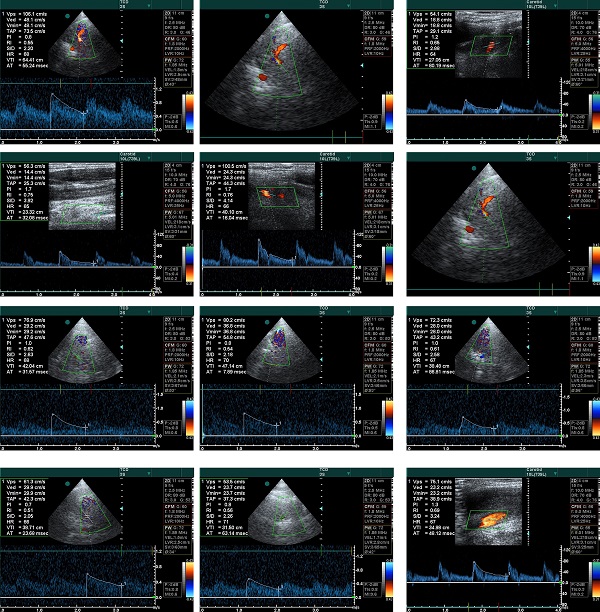

Para que os nossos pacientes beneficiem do melhor serviço possível, a Vethelp coloca ao seu dispor um aparelho de RX de alta frequência, que permite obter radiografias de qualidade em pacientes de qualquer dimensão e um Ecógrafo Doppler fixo, equipado com sondas que permitem realizar ecografias abdominais e ecocardiografias. Sendo que um exame não substitui o outro, pretendemos que ambos se completem, com o objetivo de elevar a qualidade e precisão diagnósticas.